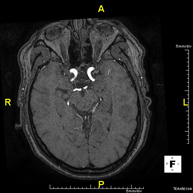

- RM Cerebral (craneal)

Prueba diagnóstica no invasiva que consiste en la obtención de imágenes de alta definición anatómica del cerebro mediante el empleo de un campo electromagnético y ondas de radio (con un emisor y un receptor). No utiliza radiación ionizante. Indicaciones: problemas vasculares, pérdida de memoria, epilepsia, cefalea, malformaciones, sospecha de tumor, meningitis. - RM Cais

Prueba diagnóstica no invasiva que consiste en la obtención de imágenes de alta definición anatómica de las arterias cerebrales mediante el empleo de un campo electromagnético y ondas de radio (con un emisor y un receptor). No utiliza radiación ionizante. En la mayoría de los casos es necesario el empleo de contraste paramagnético (Gadolinio). Permite un estudio angiográfico no invasivo gracias a la inyección de Gadolinio con posterior reconstrucción en 2D y 3D, gracias a estaciones de trabajo especializadas. Indicaciones: malformaciones vasculares, aneurismas de arterias cerebrales, arteriosclerosis. - Angio-RM troncos supraaórticos